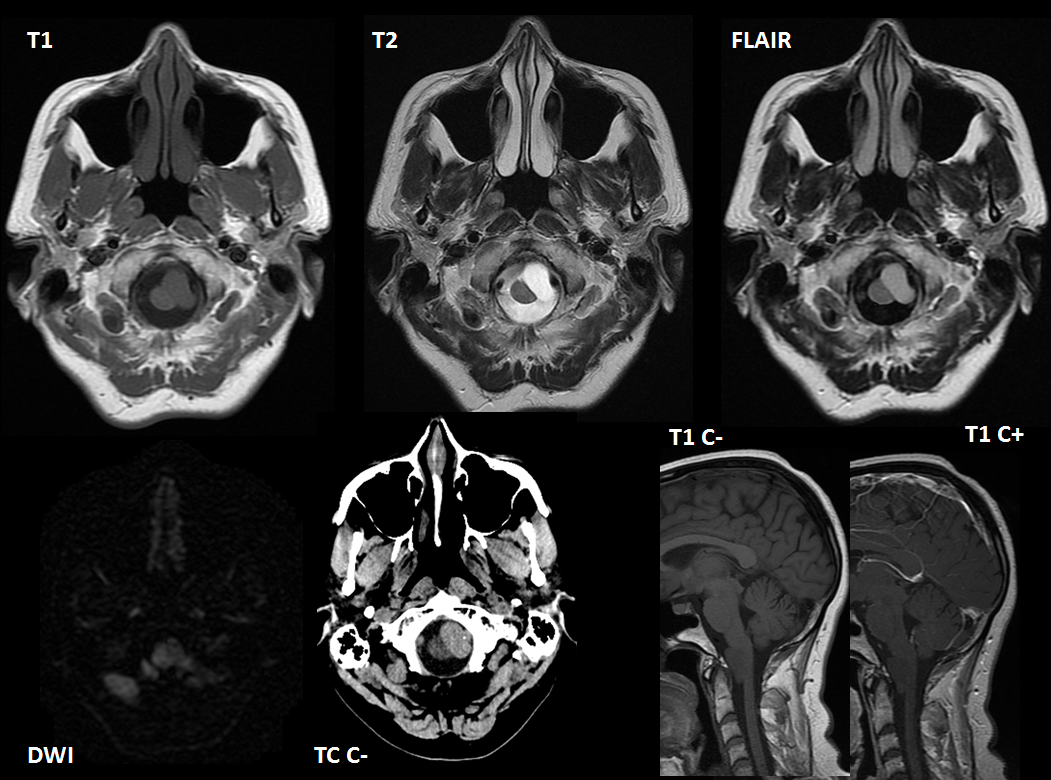

Paciente de 46 años de edad, asintomático. Se le realizo TC debido a traumatismo, posterormente se amplio estudio mediante RM.

En TC sus características son variables, aunque general mente es más denso que el LCR; sus características dependen del grado de contenido proteináceo.

Respecto al LCR la mayoría son iso-hiperintensos en T1 y típicamente hiperintensos en T2 y FLAIR. Pueden no tener restricción en DWI o mostrarla en grado leve. Generalmente no muestran realce tras administrar contraste intravenoso.